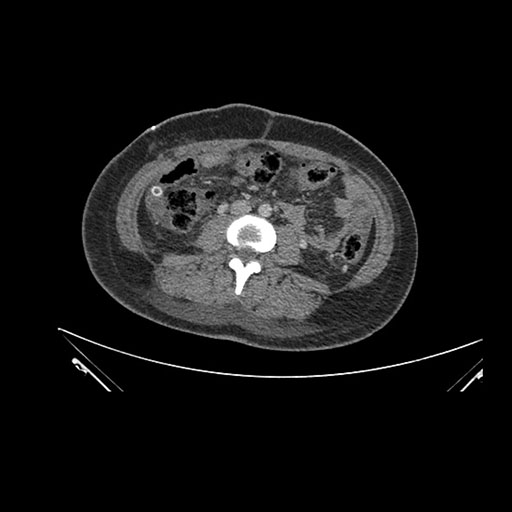

Imaging Analysis

Look through the patient's CT scan to identify any areas of concern for the necessary procedure.

Coronal Arterial

Based on initial findings, which issue(s) would you be most concerned about?